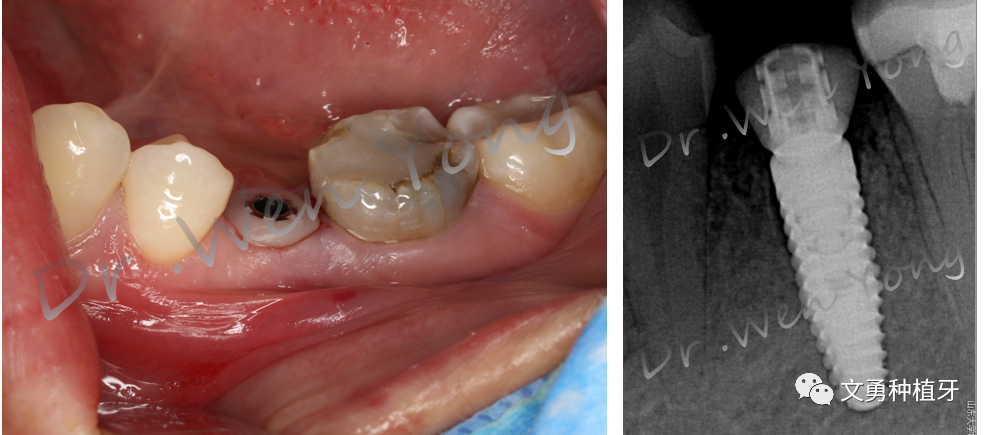

1、术前口内照片:75乳牙滞留

2、术前CBCT示:75根尖周低密度影,颊侧骨板完整

5、戴个性化愈合基台,颈袖口完整;术后影像学照片示:个性化愈合基台就位

Part2 术后38天永久修复